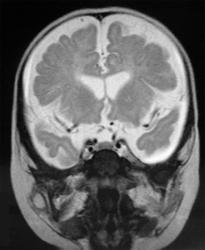

МРТ головного мозга

• Выраженное расширение субарахноидального пространства над лобными долями, обусловленное уменьшением объема лобных долей;

• Атрофия белого вещества;

• Изменение паттерна извилин: Имеются участки, где четко видны мелкие извилины, их количество увеличено по сравнению с нормальным. На других участках, напротив, извилины плоские, широкие;

• Граница между белым и серым веществом четко не дифференцируется;

• Сильвиева щель расширена, больше слева;

• Отчетливо выявляется зияние островка, что говорит о том, что височная доля не сформирована;

• Определяются зоны гиперинтенсивного сигнала в субинсулярных отделах;

• Желудочки расширены.

• Атрофия лобных долей;

• Смешанная гидроцефалия;

• Признаки нарушения формирования борозд лобных долей и перисильварного региона;

• Симметричная двусторонняя передняя перисильварная полимикрогирия;

• Атрофия (гипогенезия) мозолистого тела.